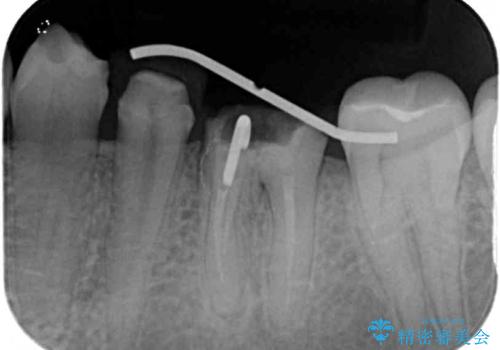

むし歯がとても大きく、歯茎に歯の一部が埋もれてしまっているため、汚れが溜まりやすくなっている状態でした。

根歯の挺出(歯を引っ張り出す部分矯正)、歯周外科処置などを行った後、オールセラミッククラウンにて補綴することとしました。